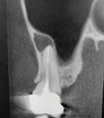

The patient returned asymptomatic at the 4-week follow-up. Nevertheless, the clinical evaluation revealed a fistula of approximately 2 mm to 3 mm in diameter in the buccal vestibule and a wound dehiscence of 3 mm (Figure 3 and Figure 4). Sinus percussion and Valsalva maneuver were negative. Panoramic x-rays revealed no suspicious radiographic changes in the residual sinus cavity or within the grafted site itself compared to the baseline radiograph (Figure 5).

Fig 3. A fistula (Fig 3) and wound dehiscence (Fig 4) were evident at 4-week postoperative follow-up.

Figure 3